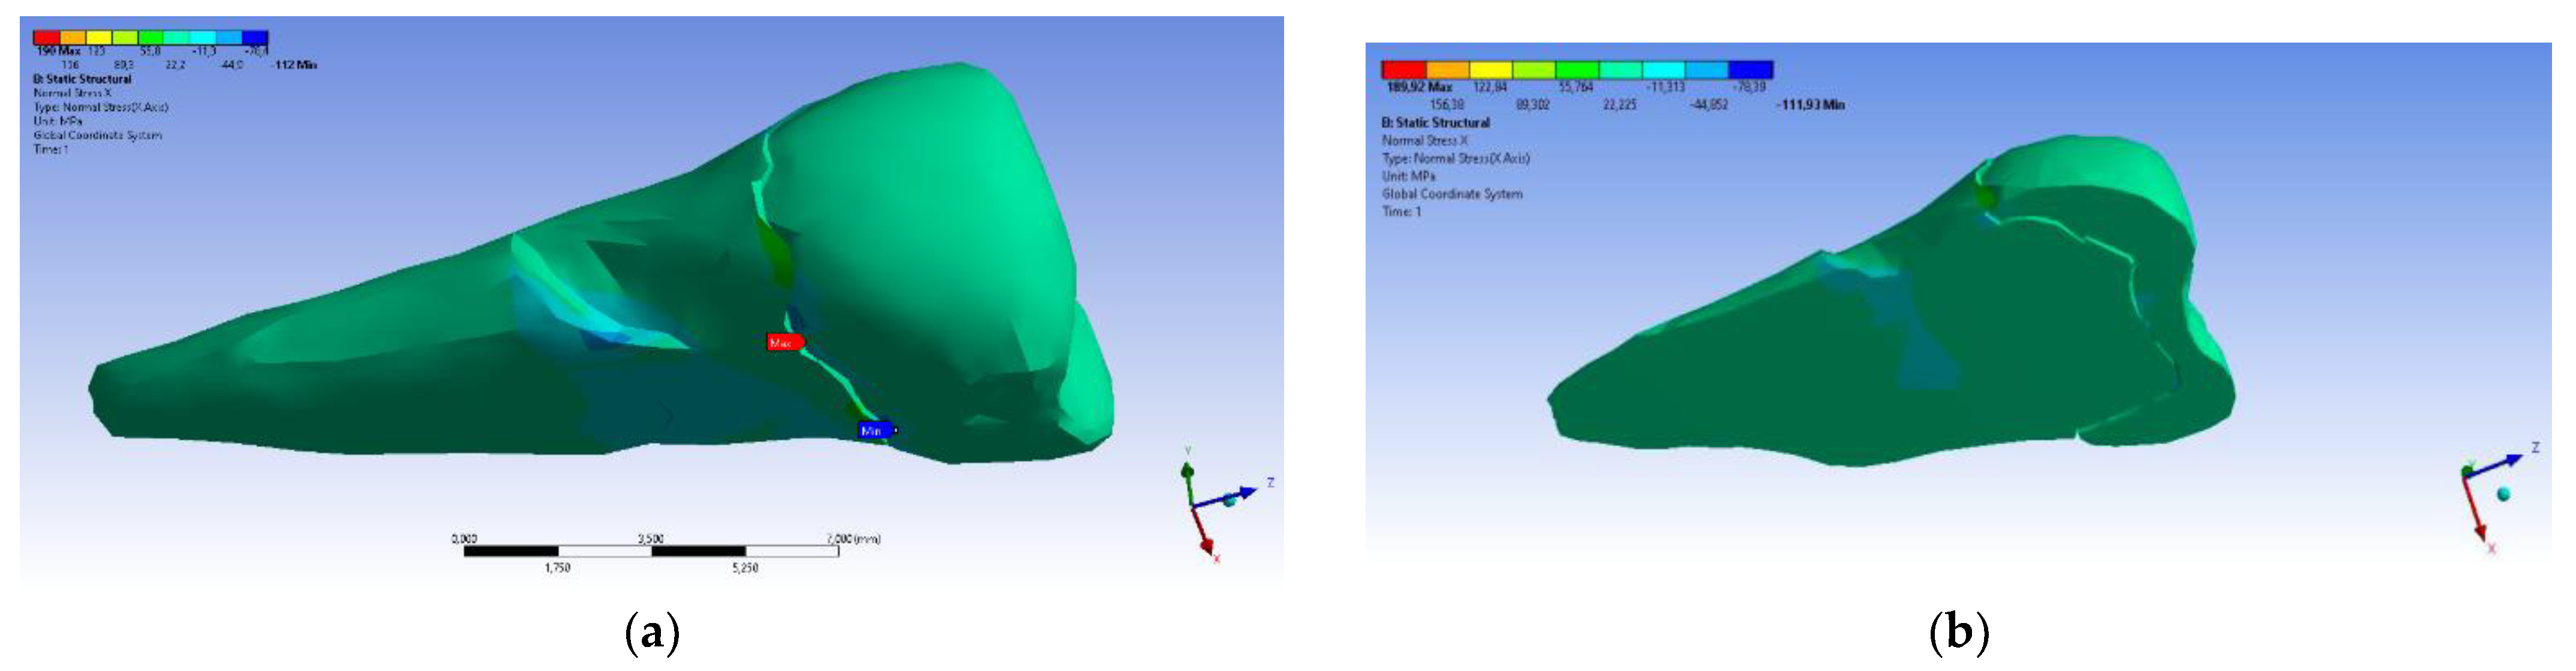

3. Finite Element Analysis (FEA) of Mandibular Right Premolars

| Total Deformation | Deformation in X Direction | Deformation in Y Direction | Deformation in Z Direction | Equivalent Stress | Normal Stress X | Normal Stress Y | Normal Stress Z | Maximum Main Stress | Minimum Main Stress | Tangential Stress XY | Tangential Stress YZ | Tangential Stress XZ | |

|---|---|---|---|---|---|---|---|---|---|---|---|---|---|

| Minimum | 0 mm | −4.24 × 10−3 mm | −2.52 × 10−2 mm | −1.56 × 10−2 mm | 1.01 × 10−6 MPa | −35.6 MPa | −57.1 MPa | −104 MPa | −15.2 MPa | −152 MPa | −43.7 MPa | −39.6 MPa | −56.3 MPa |

| Maximum | 2.77 × 10−2 mm | 3.57 × 10−3 mm | 6.98 × 10−4 mm | 4.78 × 10−3 mm | 248 MPa | 61.5 MPa | 177 MPa | 72.2 MPa | 195 MPa | 21.4 MPa | 44.2 MPa | 117 MPa | 22.2 MPa |

| Minim. in | Cementum | Cementum | Enamel | Enamel | Cementum | Cementum | Enamel | Enamel | Enamel | Cementum | Enamel | Enamel | Cementum |

| Maxim. in | Enamel | Enamel | Cementum | Enamel | Cementum | Enamel | Enamel | Enamel | Enamel | Enamel | Cementum | Cementum | Cementum |